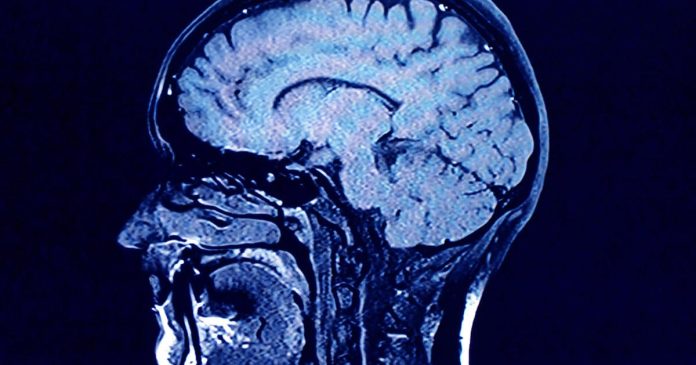

Human brains comprise greater concentrations of microplastics than different organs, in accordance with a brand new research, and the quantity seems to be rising over time.Â

Within the research, revealed Monday within the journal Nature Medication, College of New Mexico Well being Sciences researchers discovered microplastics in human brains have elevated 50% over the previous 8 years. Additionally they discovered that folks with dementia had as much as 10 instances as a lot plastic of their brains as everybody else.

The research in contrast liver, kidney and mind tissue samples from autopsies performed in 2016 and 2024, and located “considerably greater concentrations” within the 2024 mind tissue. The researchers additionally performed related evaluation on older and more moderen autopsies for individuals who died with confirmed dementia diagnoses, and located “far higher” concentrations.

Whereas it is unclear how particles are literally being transported into the mind, Campen mentioned the dimensions of the micro- and nanoplastics, measuring 200 nanometers or much less, aren’t a lot bigger than viruses and subsequently sufficiently small to cross the blood-brain barrier.